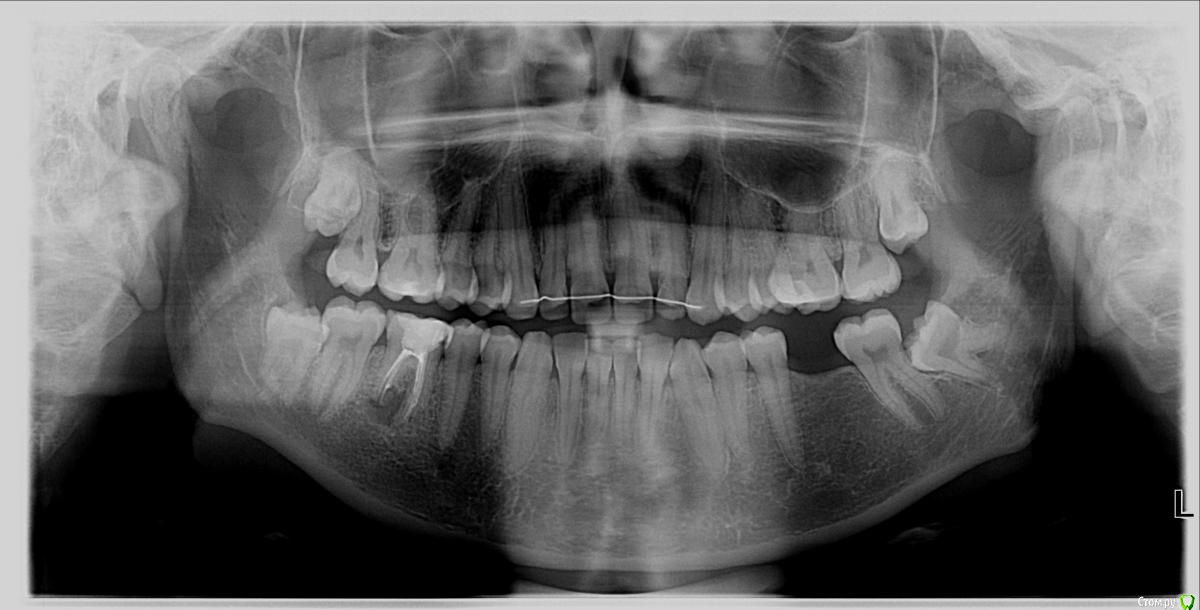

10 лет назад удален 6 нижний зуб слева (верхняя шестёрка за это время опустилась, снизу "лёг" восьмой зуб и "таранит" седьмой). Так же давно плохой 6 нижний зуб справа, долго лечила его, не вылечили. Сейчас под ним киста и его на удаление. В дальнейшем собираюсь поставить 2 импланта на обе шестёрки снизу.

Через 3-4 недели предлагается за один день удалить 6 зуб снизу справа, удалить под ним же кисту, сразу внедрить имплант. Наблюдать и ждать, пока приживётся, затем коронку. Следом надеваю брекет-систему (это наверное в тему к ортодонтам, но я допишу целиком уже клиническую картину), подтягиваю верхнюю просевшую шестёрку слева и заодно ставят пружину снизу, чтобы немного раздвинуть место под имплант между 7 и 5 зубами слева снизу. Попутно с брекет-системой через продолжительное время снизу слева на шестёрку ставится второй имплант. И последним этапом удалят 2 восьмёрки справа (обязательно?).